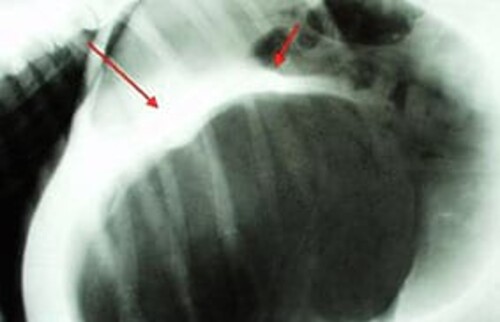

Magendrehung, Röntgenbild vom Bauch, Faltenbildung ist durch Pfeile gekennzeichnet.